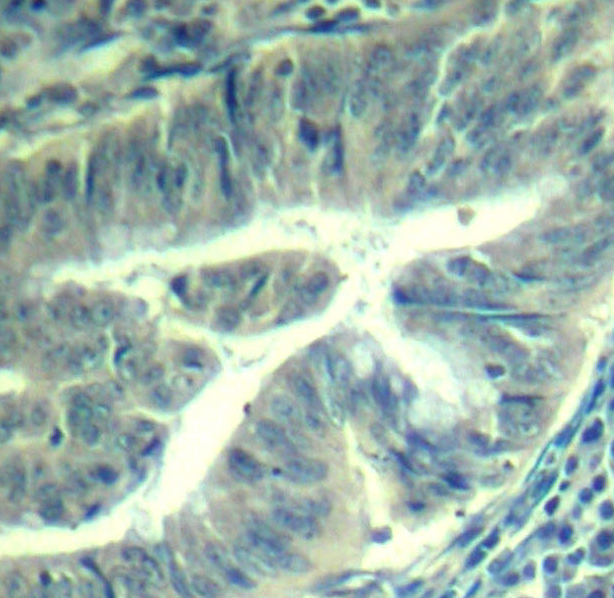

• AP0289: image 2

Immunohistochemical analysis of paraffin-embedded human colon carcinoma tissue using Phospho-CDK6-Y24 antibody.